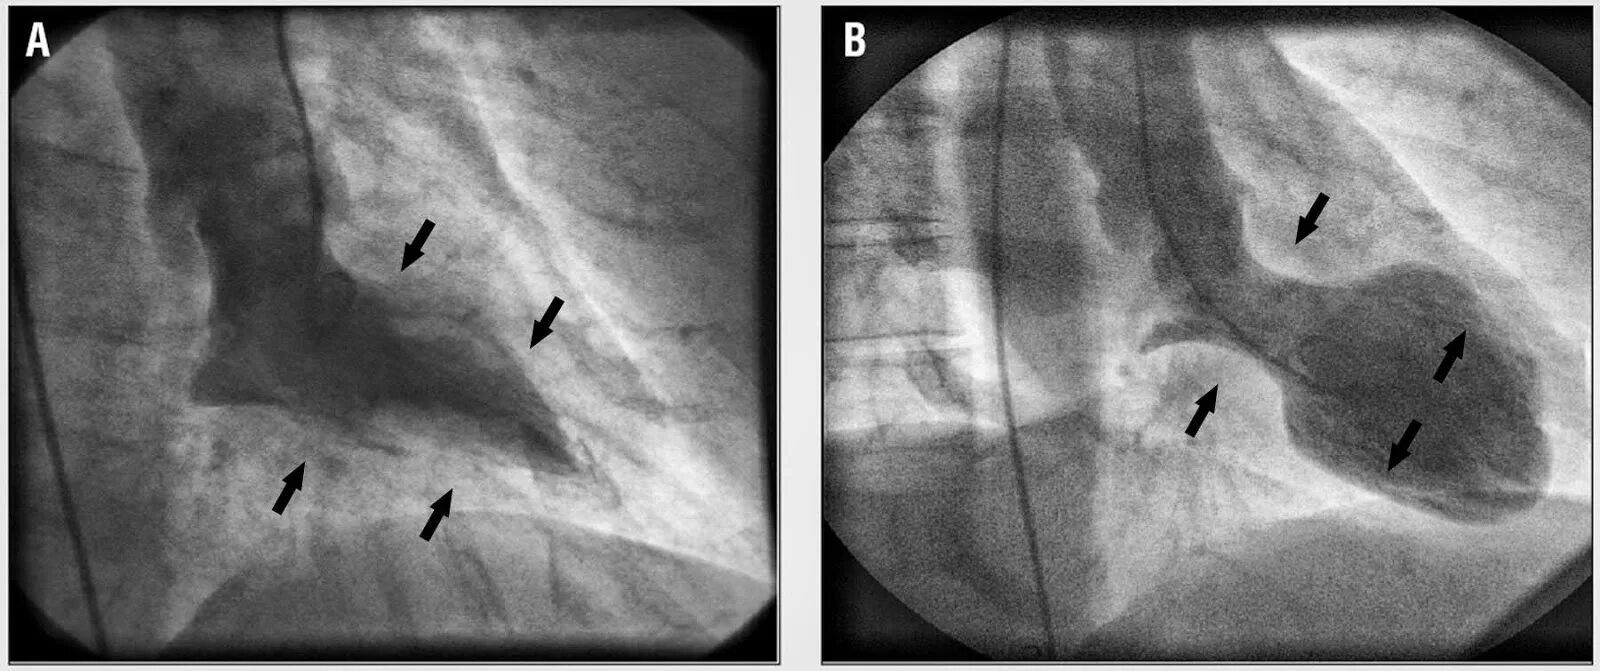

Синдром разбитого сердца симптомы